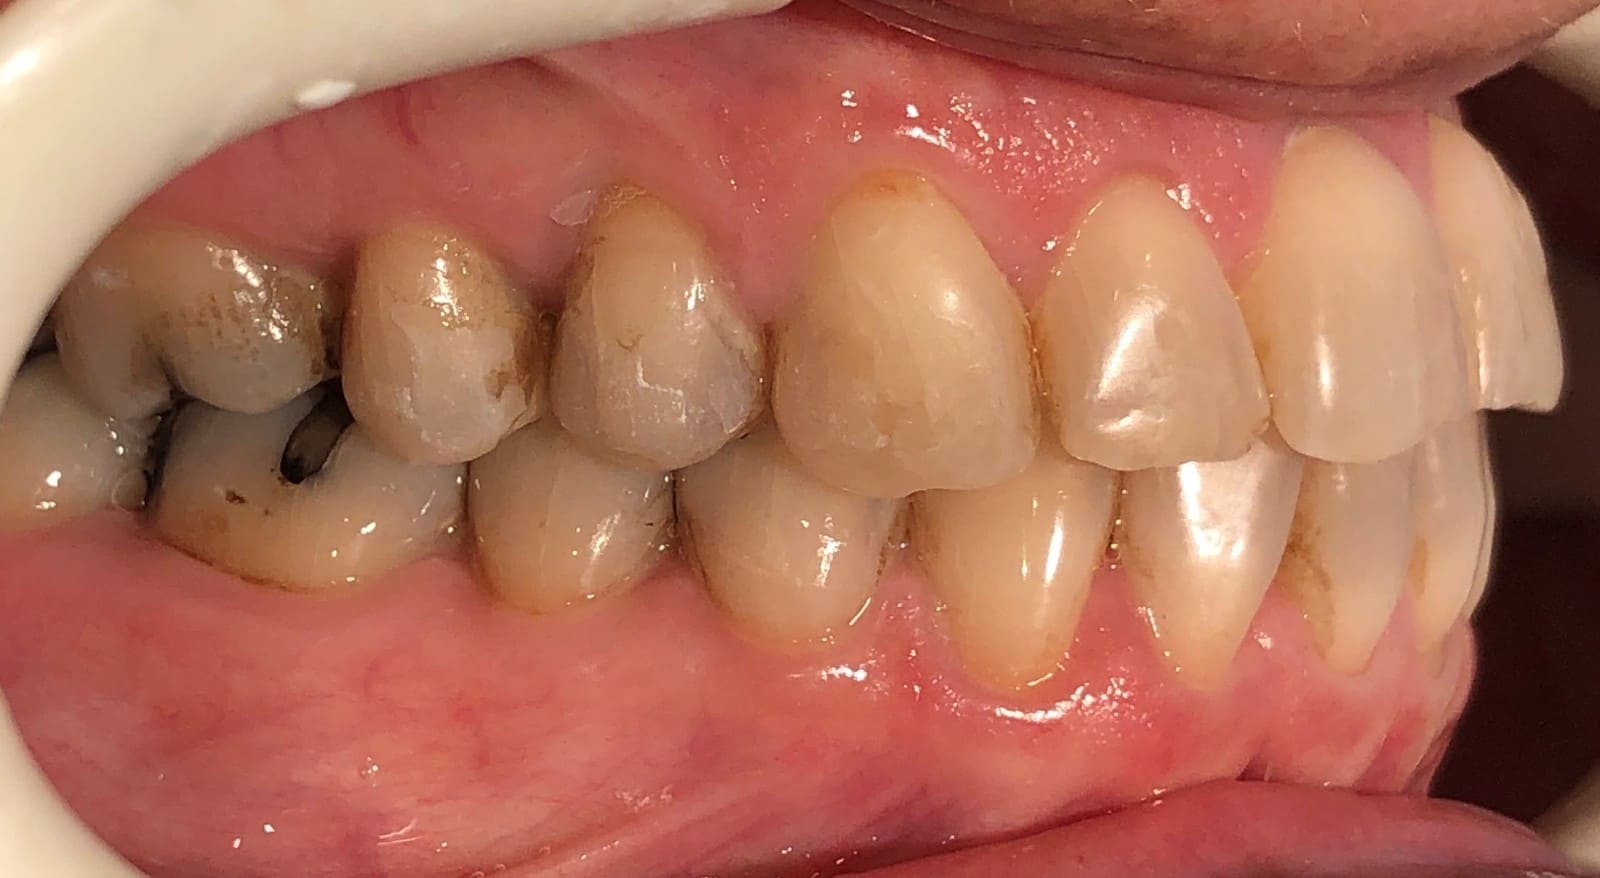

Initial

Final

Results achieved

- Class I relationship achieved

- Functional canine guidance on both sides

- Anterior crossbite corrected

- Normal overjet and overbite achieved

- Midlines coincident

- Proper axial inclination of incisors

- Curve of Spee leveled

- Arches aligned and coordinated

- Arch form improved

- Aesthetic smile line was achieved

- All treatment goals were achieved case